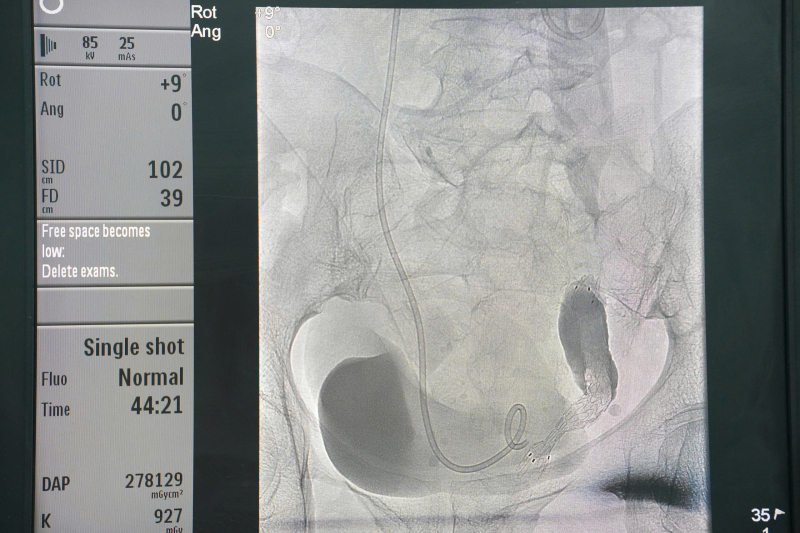

Kỹ thuật được chỉ định cho các trường hợp tắc nghẽn đường bài xuất tiết niệu gây giãn đài bể thận, có thể do u xâm lấn hay chèn ép làm hẹp niệu quản hoặc sỏi … và các bệnh nhân này không thể đặt sonde JJ theo đường ngược dòng. Dưới sự hỗ trợ của hệ thống DSA hiện đại, bác sĩ can thiệp tiếp cận bể thận qua da, đưa stent niệu quản hoặc sonde JJ chính xác, an toàn, giúp giải phóng tắc nghẽn, bảo tồn chức năng thận và cải thiện nhanh tình trạng người bệnh.

Hình ảnh: stent niệu quản trên hệ thống chụp mạch số hóa xóa nền (DSA).

Đây là phương pháp

cứu cánh cho các trường hợp đặt sonde JJ

ngược dòng thất bại tránh cho bệnh nhân một cuộc phẫu thuật mở, kỹ thuật

này có nhiều ưu điểm vượt trội so với phẫu thuật như: ít xâm lấn, giảm đau, hạn

chế biến chứng, thời gian thực hiện nhanh và rút ngắn thời gian nằm viện.